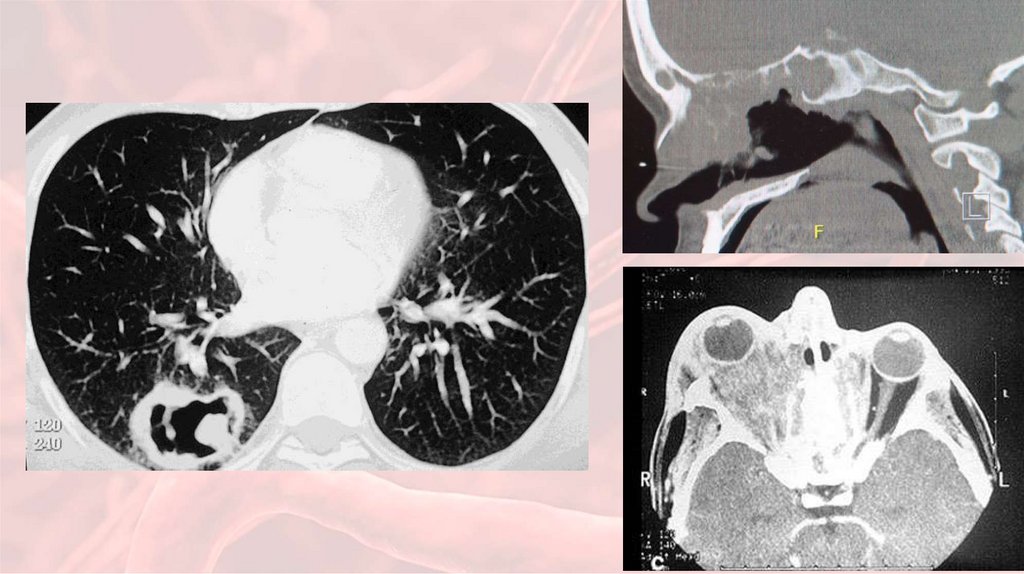

25. Чем болеет пациент?

• Выполнена КТ:

30. Клинические исследования

2. Рентгенография и

КТ придаточных

пазух носа и лёгких;